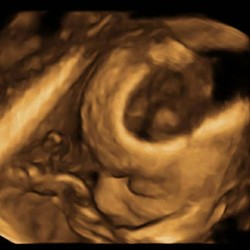

Bij mijn vorige zwangerschap. Dochtertje is nu b ijna 9 maanden. Had ik dat dus ook. Misselijk gevoel constant en dan een soort brok in me keel. Heeft heel me zwangerschap aangehouden maar is gewoon een kwaaltje. Daar kan je niks aan doen. Wel erg vervelend. Ik moest vaak boeren om een beetje eventjes ervan verlost te zijn. Dus ik dronk spa rood.

Droge Hyperemesis gravidarum?? Google maar eens. Krijg je wel drinken binnen?

Je kan even googelen op globusgevoel. Ik zou het toch gewoon even met je huisarts bespreken want het kan ook iets psychisch zijn (veel zorgen maken kan leiden tot een globusgevoel) maar wij zijn natuurlijk geen dokters en je verdient de beste zorg, helemaal nu je zwanger bent. Veel sterkte!

Amai de hele zwangerschap. Ik lig momenteel al hele week in men bed omdat ik me zo slecht voel. Ik hoopte dat dit vooral de eerste maanden zou aanhouden. Ik moet idd ook regelmatig boeren.

Dit heb ik door hooikoorts heel naar dat gevoel! Kan ook spanning zijn